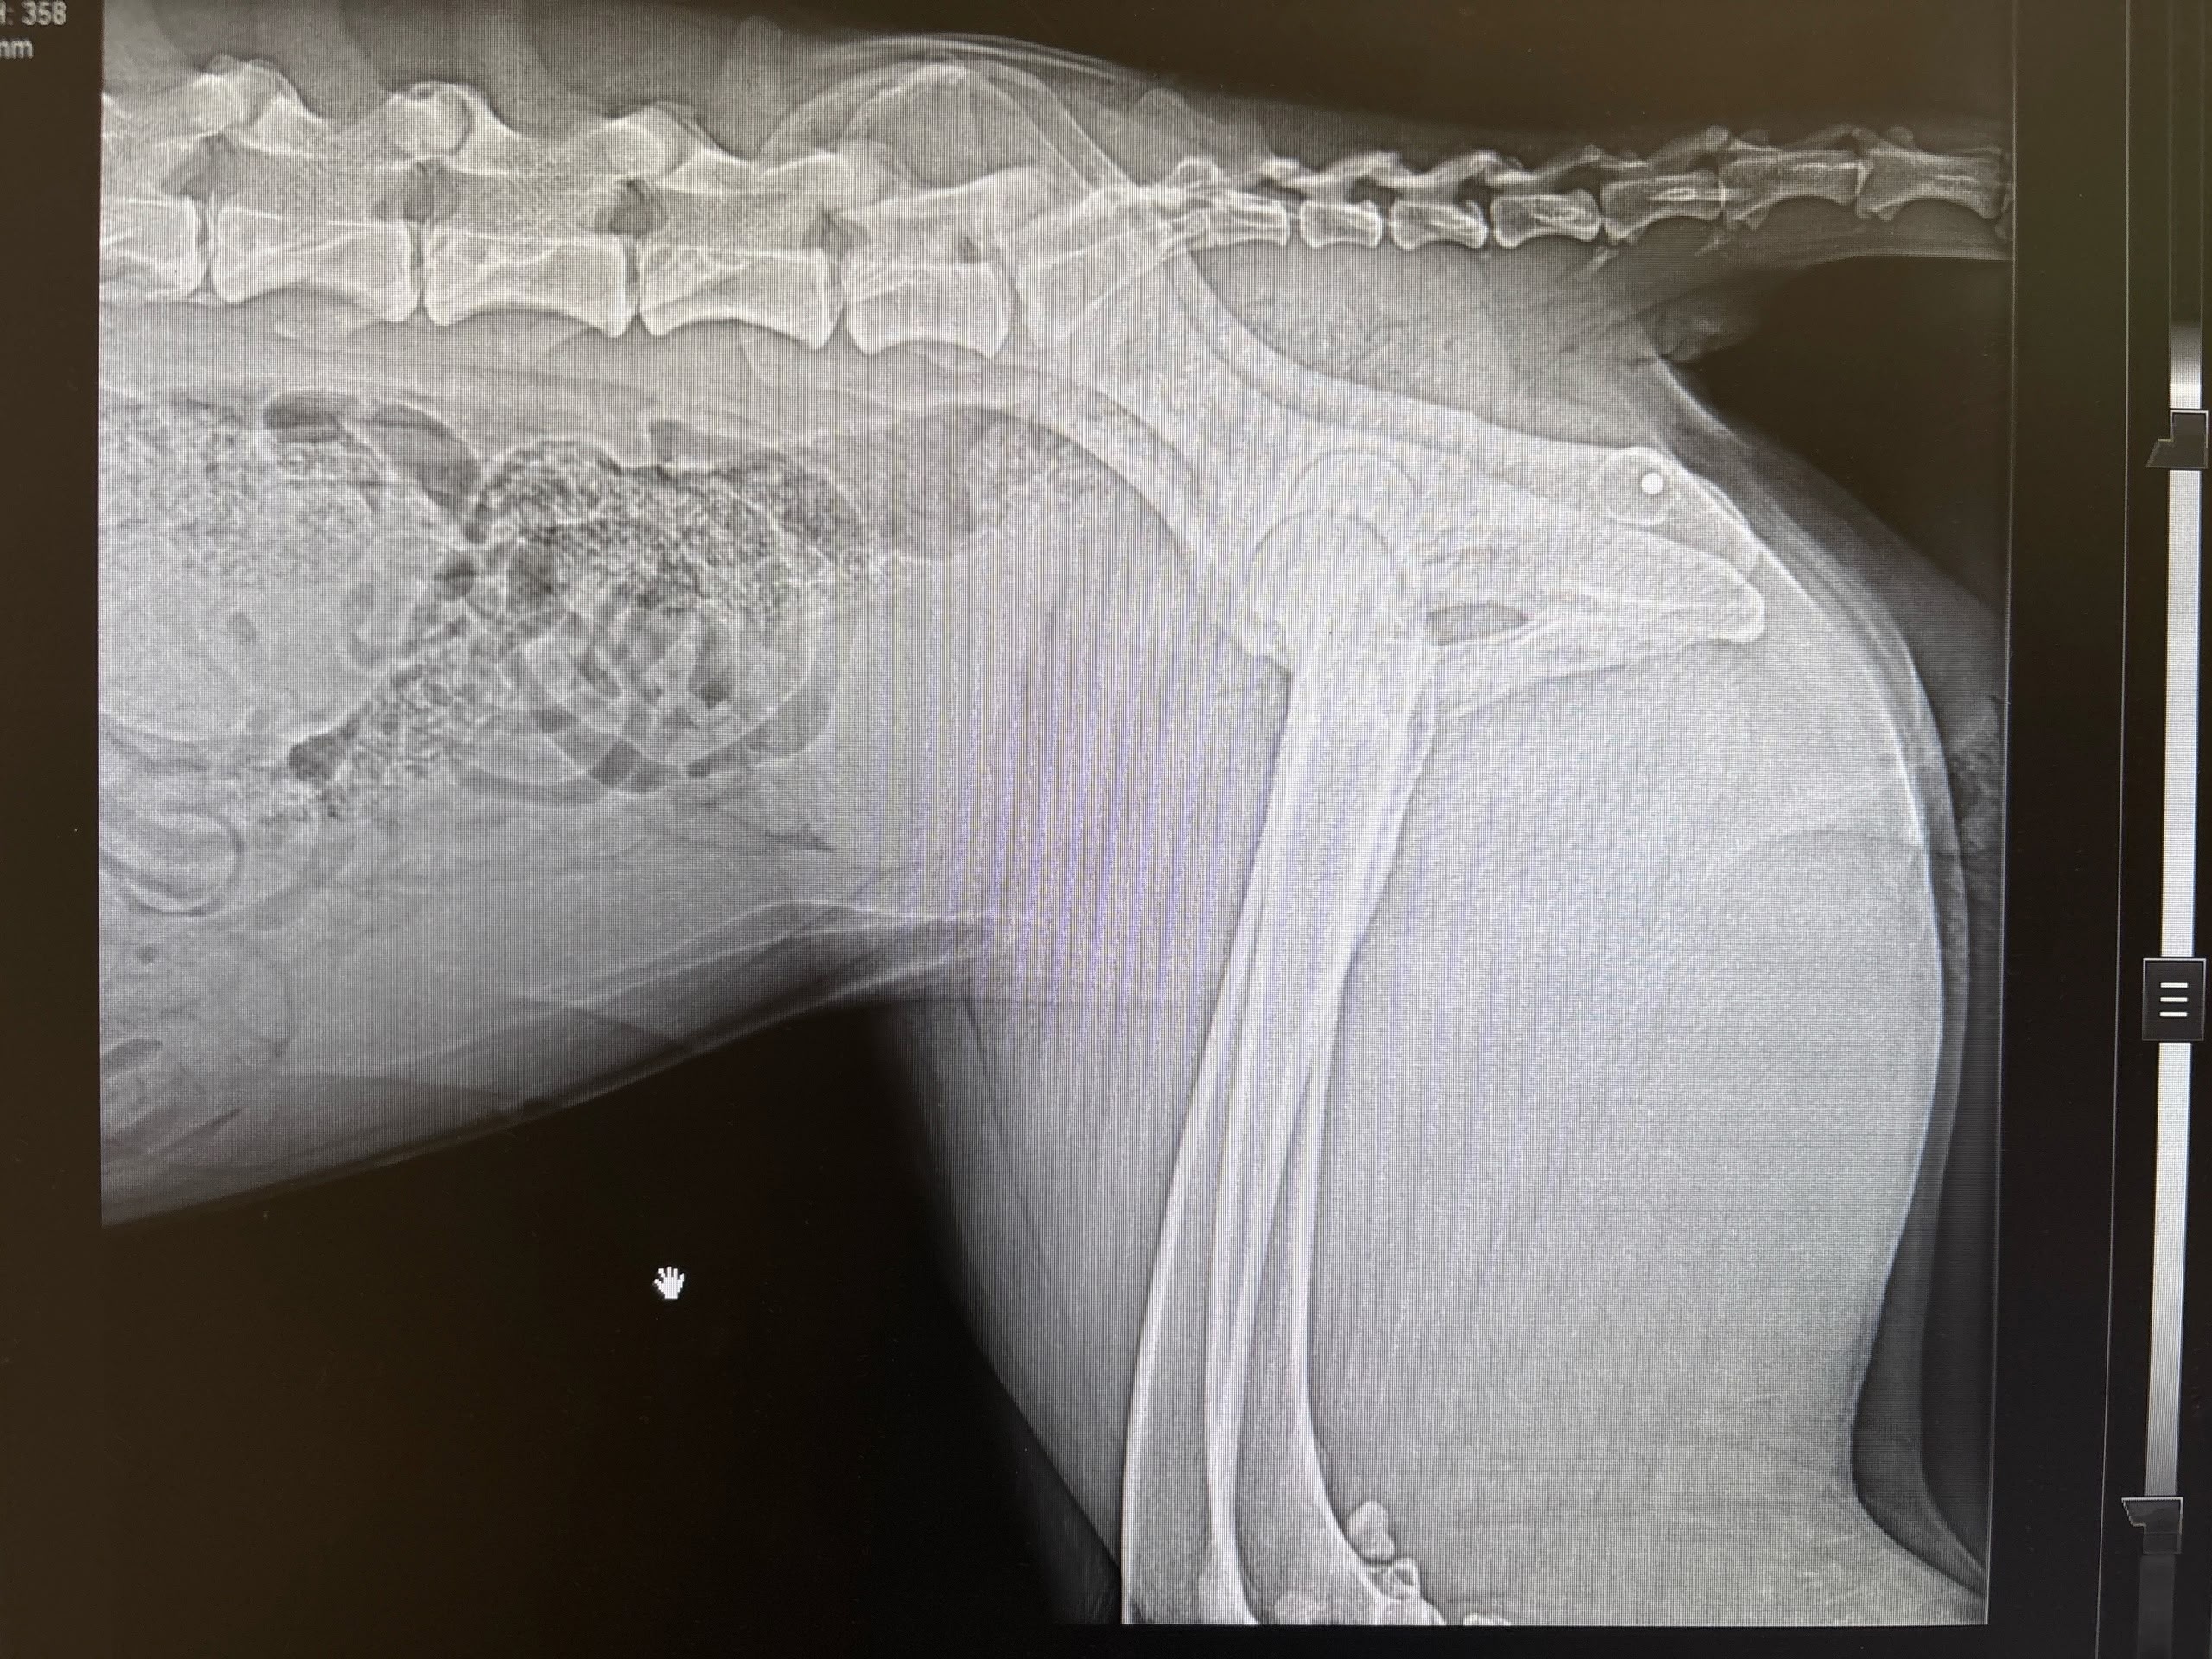

Мужчина по имени Вадим рассказал 78.ru, что отвел своих собак домой, а затем вернулся и при помощи шлейки кое-как вытащил пса, а затем передал волонтерам. Те отвезли его в выборгскую ветклинику, где рентген показал наличие дроби в позвоночнике и мягких тканях.

Позже Вадим нашел еще одну простреленную собаку, сучку, в поле и на этот раз сам отвез ее ветеринарам. И вновь на снимке медики увидели дробь.